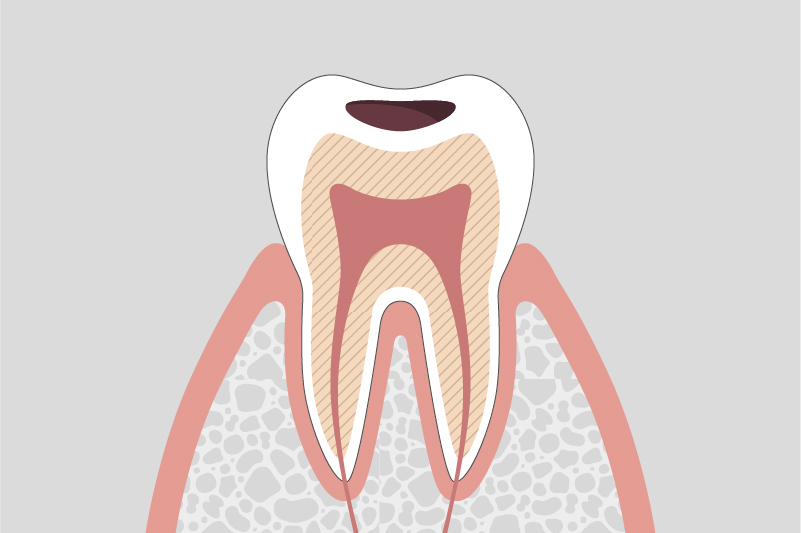

C2.

象牙質に達する虫歯

冷たいものや甘いものでしみることがある。